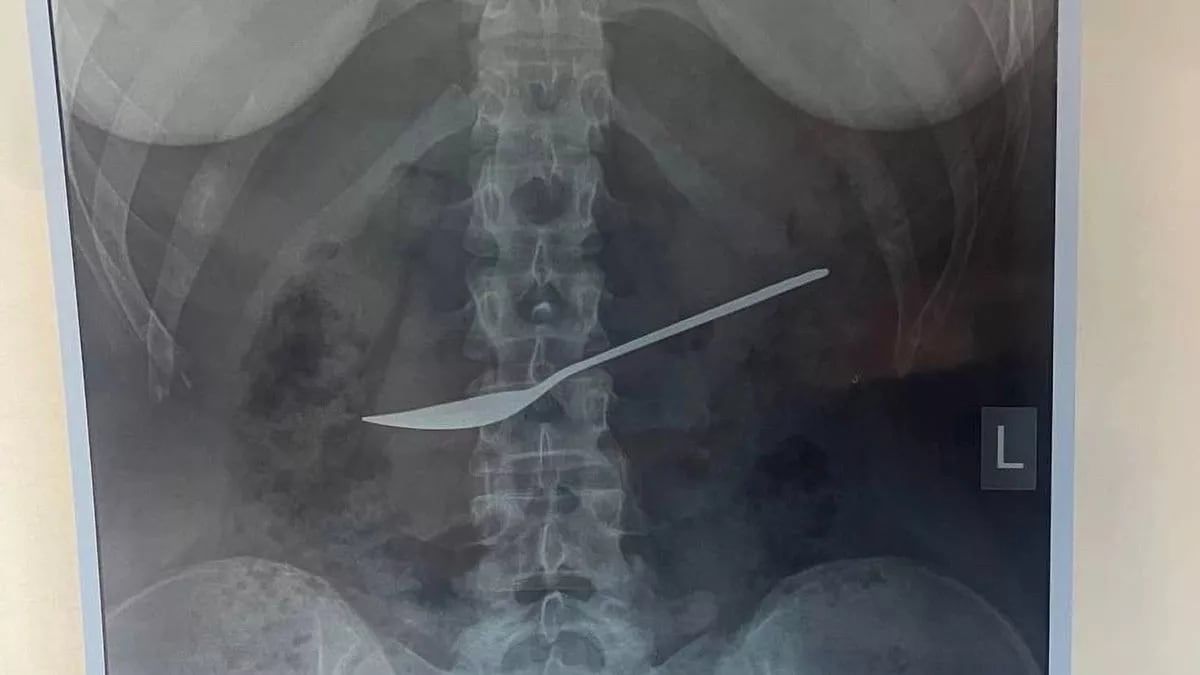

Según informó el Mirror, el hecho tuvo lugar en el hospital Clínico Regional Estatal de Vologda, en Rusia. Al ver las imágenes, los profesionales descubrieron que tenía una cuchara en la panza.

Inmediatamente, la niña fue sometida a una cirugía de emergencia. El cubierto tenía 20 centímetros de largo.